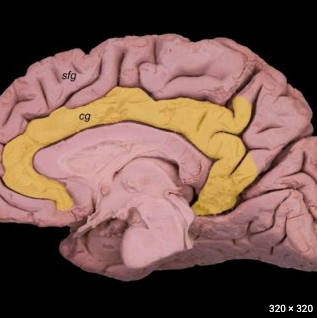

Where is the cingulate gyrus in the brain? [1]

Which structure does it lie directly above? [1]

Lies above the corpus callosum